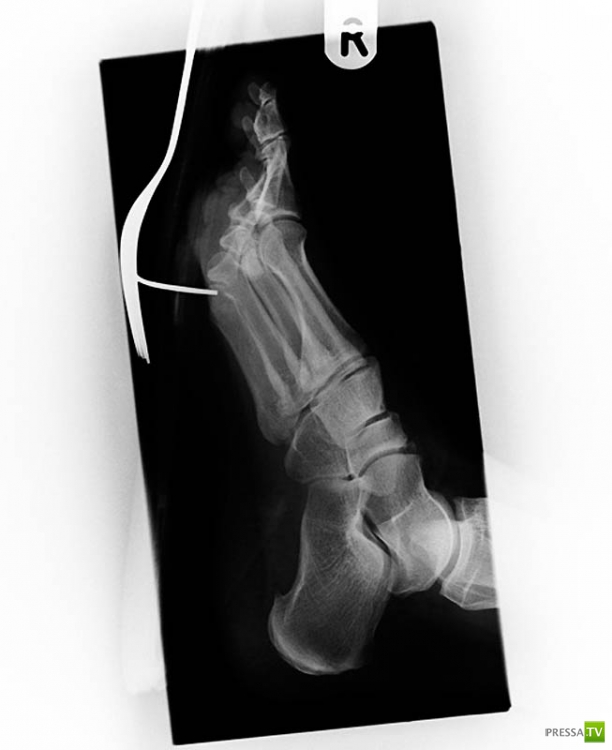

Старинный рентгеновский снимок ступни солдата англо-бурской войны (1899-1902) с огнестрельным ранением. Пуля застряла между большим и вторым пальцами.